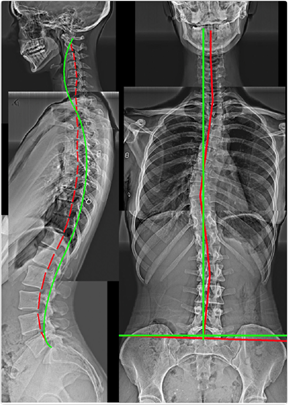

Case 1 — 37yo Male: Posture & Hip Tightness

Figure 1. Right Thoracic Lean, Right Head Translation, Increased Pelvic Tilt, Lumbar Hyperlordosis, Thoracic Hyperkyphosis, Anterior Head Translation, Cervical Hypolordosis. Multiple intersecting deformities — none detectable without X-ray